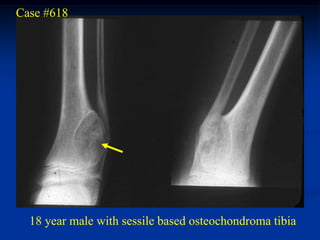

Case #618

18 year male with sessile based osteochondroma tibia